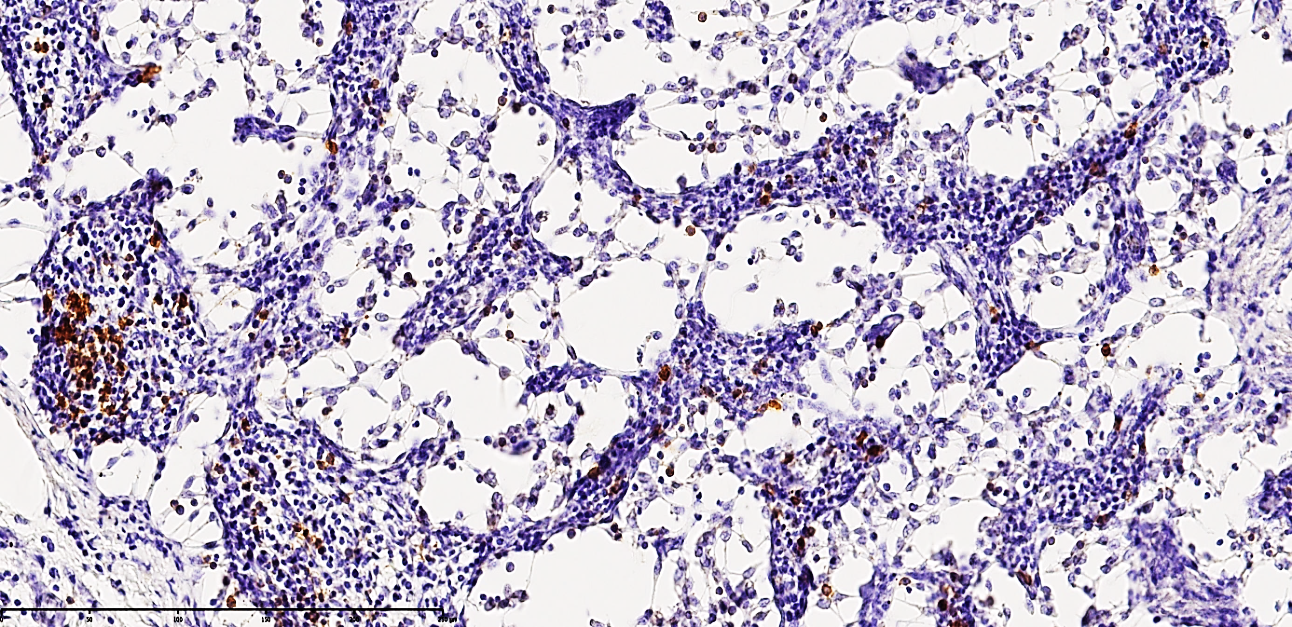

| Figure 2. Mesenteric lymph node of a 24-year-old patient with acute secondary peritonitis. The micrograph demonstrates a moderate-to-low positive immunohistochemical expression for the CD68 3 marker. In the paracortical regions, a sparse distribution of T-lymphocytes is observed, characterized by a distinct yellow-brown cytoplasmic staining. Staining: DAB chromogen. Magnification: 10х10 |

The CD68 marker, primarily an adhesive membrane protein of macrophages, identifies these cells as they migrate from affected tissues through lymphatic vessels into the regional lymph nodes. In this study, out of 33 patients, 27 (81.81%) exhibited moderate positive expression, while 6 (18.18%) showed low positive reactions. These shifts confirm that a critical deficiency of immunocompetent cells within the lymph node triggers a compensatory increase in the phagocytic activity of macrophages. The observed enlargement of CD68-positive macrophages to giant proportions, characterized by dense, homogeneous, dark basophilic cytoplasmic inclusions, indicates an advanced state of phagocytosis following the ingestion of tissue debris. This phenomenon underscores that during the initial 1–3 days of acute peritonitis, a forced lymphatic drainage process occurs alongside the massive mobilization of lymphocytes toward inflammatory foci.Furthermore, a massive proliferation of CD68+ macrophages coupled with a profound depletion of lymphocytes is observed within the cortical and medullary layers, the paracortical zones, and the lymphoid follicles. This not only signifies the progression of secondary immunodeficiency but also reflects heightened proliferative activity of reticulocytes and an increase in fibroblasts and histiocytes. The chaotic formation of numerous reticular processes within the medullary cords, arising in response to the sharp decline in lymphocytes, indicates an intensifying process of massive delimphatization. Simultaneously, the accumulation of phagocytically active macrophages represents an attempt to fill the structural voids caused by nodal collapse, which is further exacerbated by the development of interstitial edema. The fraying and plasmatic swelling of the reticular fibers forming the medullary cords, combined with excessive fibroblast proliferation, allow for the prediction of burgeoning lymphoreticulosis and lymphoreticulosclerosis within the medullary substance.The drastic reduction of CD20+ B-lymphocytes, the delimphatization of lymphoid follicles in the cortical zone, and the predominant accumulation of macrophages within secondary follicles collectively indicate the development of focal lymphadenitis, a finding corroborated by neutrophil accumulation along the marginal surfaces of the follicles. In the paracortical zones, the residual small lymphocytes and lymphoblasts are found to have undergone incomplete apoptosis. Numerous reticulocytes and phagocytically active CD-receptor macrophages are identified surrounding these apoptotic and necrobiotic cells. Among the 33 cases studied, 11 patients showed a moderately low positive reaction for the CD20 marker, while 21 patients exhibited a completely negative reaction, further confirming the manifestation of severe secondary immunodeficiency as detailed above.